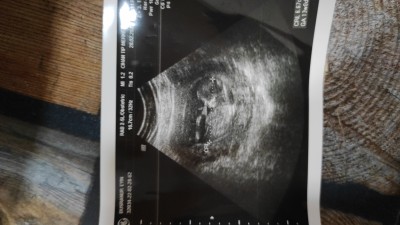

Kızlar merhaba bugün doktora gittim 13+1 1 hafta sonra gel dedi cinsiyet için. Çok heyecanlıyım meraktan ölüyorum:)) keseye göre cinsiyet diye bişey gördüm az önce internette,

imageböyle birşey varmı yorumlarınızı alabilir miyim bende ilk kez duydum :)

Gebelik haftası 13

Fasulye gibiyse erkek diye okudum int. Ve benmkide fasulye gibiydi erkek

Benimki daha yuvarlak sanki ama bı önceki ultrason resminde fasulye gibiydi :)